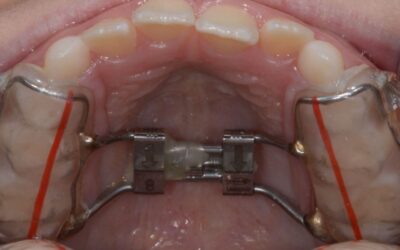

Does My Child Need an Expander?

This is one of the most common questions parents ask when their child visits the dentist or orthodontist. Many children between the ages of 8 and 10 are fitted with expanders, which can make parents...